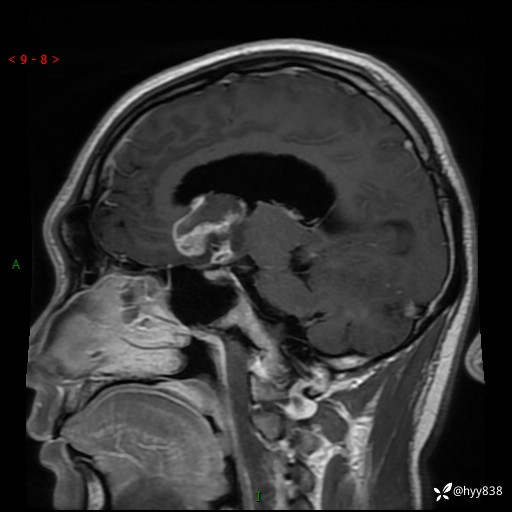

颅脑MRI平扫+增强